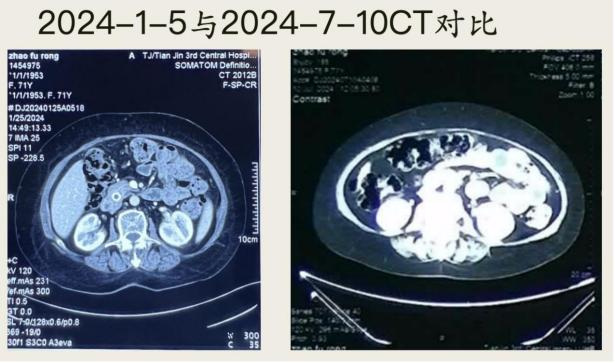

三年前,天津的赵阿姨查出胰腺癌,由于阿姨患有20多年的糖尿病,她没有选择手术治疗,而是直接找到刘鲁明教授接受中医治疗。

没想到的是,经刘鲁明教授团队治疗仅3个月后,再做强化CT复查,肿瘤已经消失不见了!现在的赵阿姨,胃口好了,体重也增加了,已经可以像普通老人一样正常生活。

(图三为治疗五个月后,肿瘤消失影像)